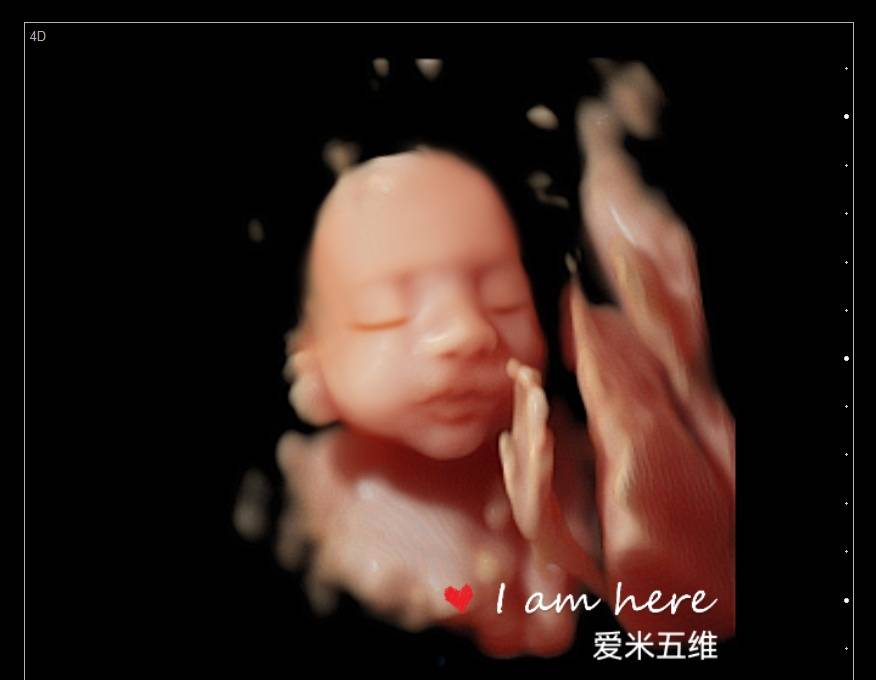

第一次五维看到了宝宝,好可爱,看的非常清楚,打印出来的照片也很清晰,第一次看到宝宝在肚子里的样子真的很激动,服务特别亲切,拍个五维还是很值得的

爱米孕婴摄影有着8年的拍摄历史,经验丰富、专业技术高超、并引进最新技术设备、呈现最完美影像照片,我们秉承着以客户满意为宗旨、资深影像师为您一对一的服务,宝妈可通过大屏幕清晰看到宝宝的各种动作及表情,让您感受与宝宝初次见面的激动,留下珍贵的瞬间!